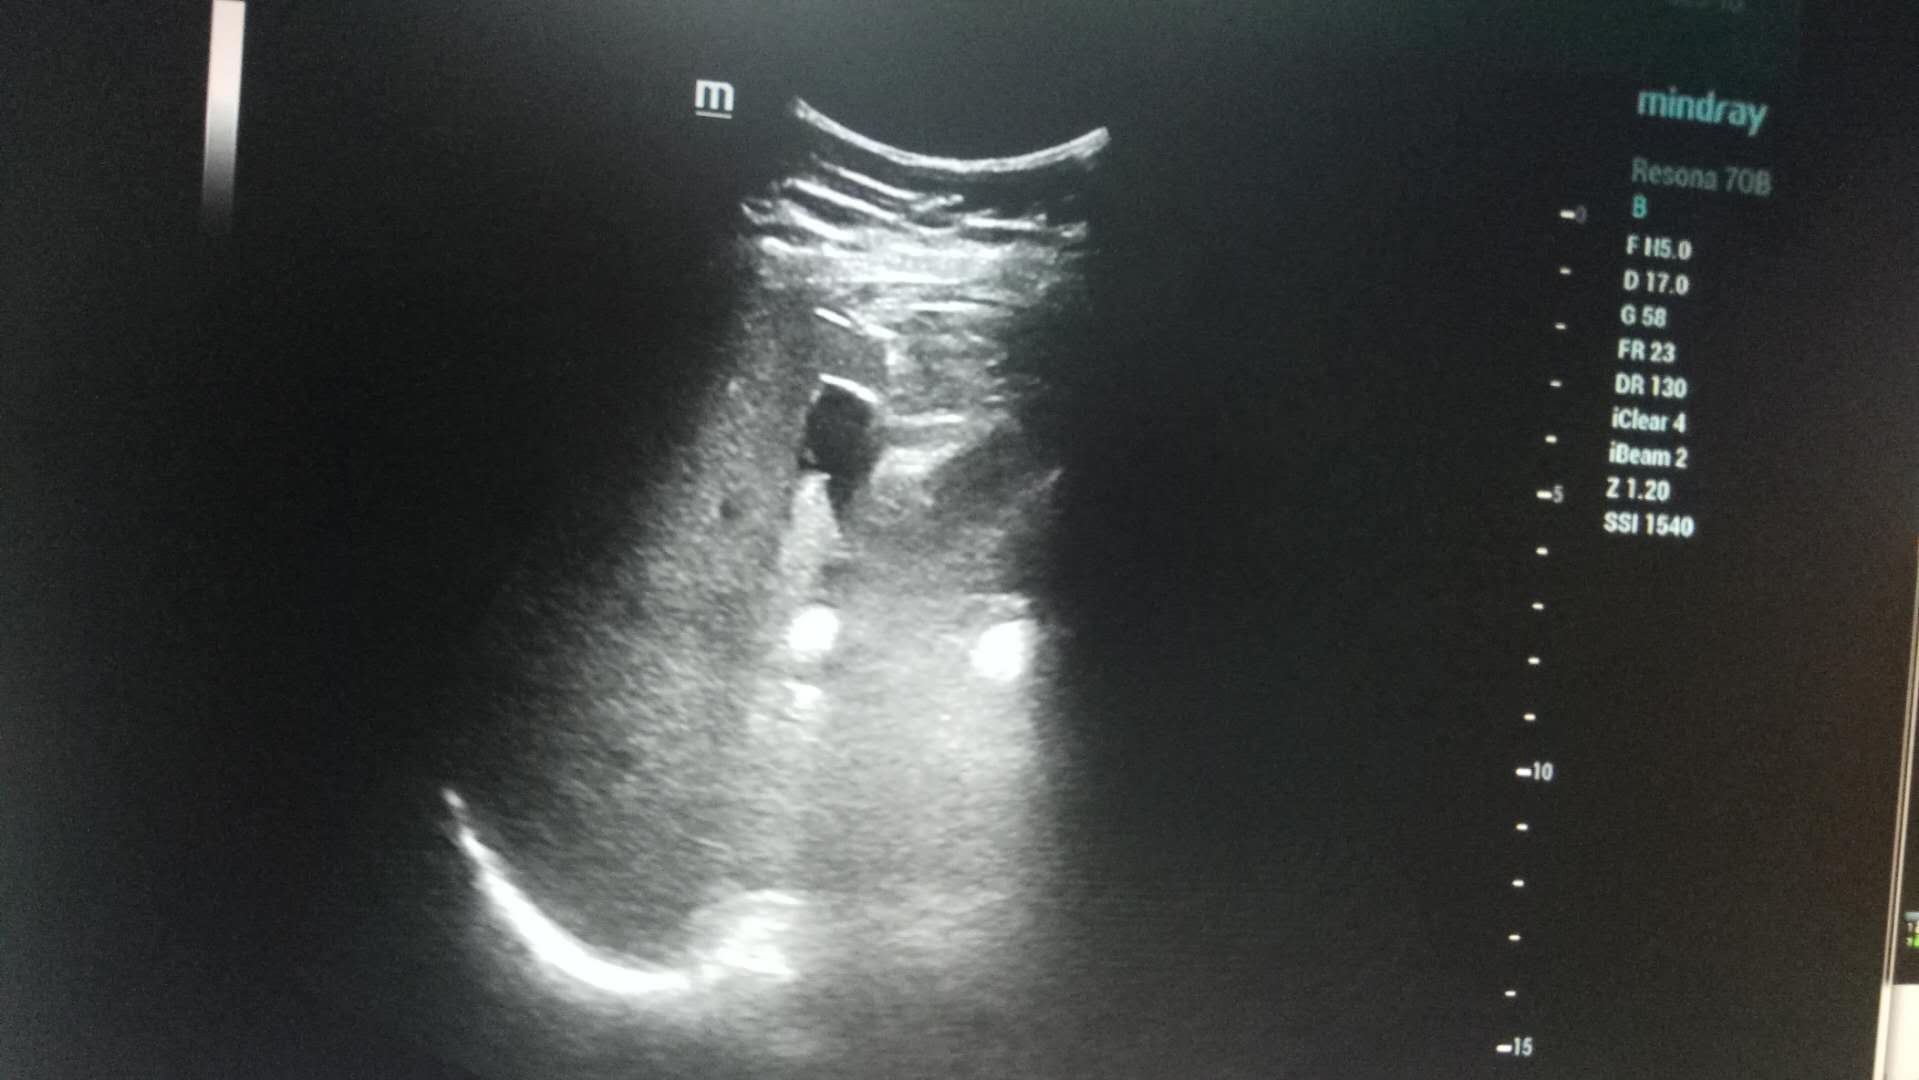

近日,成人导航 超声科在高陵区成人导航 成功开展了一例超声引导下肝囊肿抽吸硬化治疗术。患者前段时间查出肝囊肿,因开腹手术风险性大且痛苦,遂联系了高陵区成人导航 超声科,在成人导航 超声科主任展小军与对口支援医生杨艳秋的紧密配合下,短短30分钟,通过一根穿刺针,直径近7cm的肝囊肿就被完全抽吸硬化完毕,患者生命体征平稳,休息几小时后已活动自如。

超声介入微创诊疗技术是在实时超声的监视和引导下,完成各种穿刺、活检以及抽吸、插管、注药治疗等操作,达到与外科手术相当的效果,具有创伤小、恢复快、无辐射、介入治疗定位精确等优点。可治疗全身各部位囊肿,尤其是巧克力囊肿效果更佳,还有全身各部位肿瘤的活检和治疗,超声引导下微创治疗是未来医学发展方向。